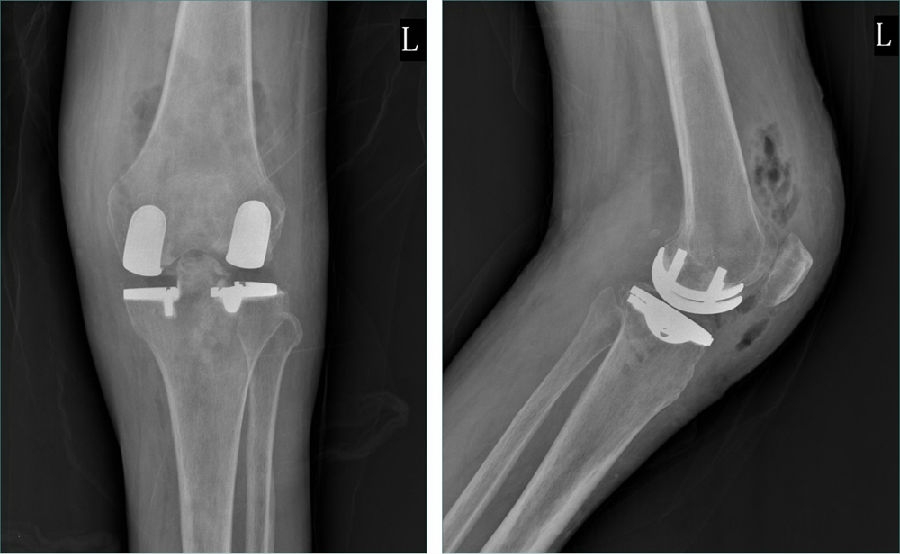

术后透视。A.正位B.侧位

术后1周X-ray片